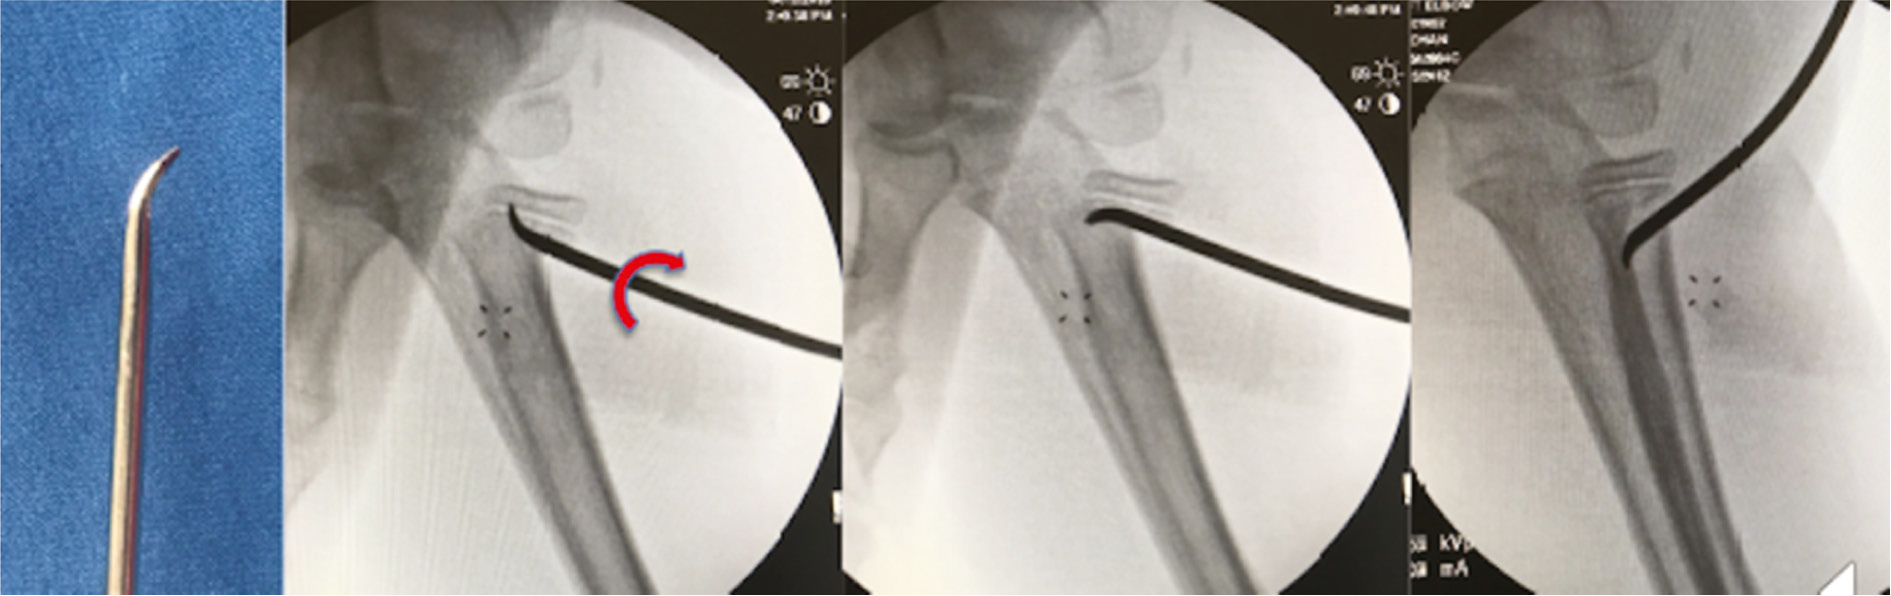

K-wires can be used for both reduction purposes and for percutaneous fixation in the management of pediatric radial neck fractures. A K-wire may be inserted into the fractured portion of the radial neck, and reduction may be achieved through leverage of the K-wire in conjunction with direct pressure on the radial head with the elbow in flexion or with the Métaizeau technique, which utilizes elastic stable intramedullary nailing (Nancy nailing) for reduction (Figure 11).45,46 Fracture fixation can then be achieved with either percutaneous pin fixation or with a retrograde elastic nail.47,48

Figure 11. The tip of a 2.4 mm Steinmann pin is bent and used to lever the radial head back. The radius can be casted or stabilized with a retrograde nail if the reduction is unstable.